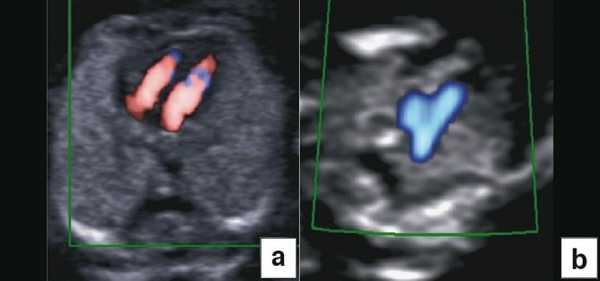

Тем не менее "базовое" УЗИ обычно дополняют исследованием в цветовом энергетическом допплеровском режиме с тщательным анализом для выявления атриовентрикулярного кровотока в четырех камерах сердца (рис. 6a) и в срезе через три сосуда и трахею (рис. 6b). Получив эти срезы, обычно можно успокоить родителей, исключив наличие тяжелых пороков сердца, таких как единственный желудочек, гипоплазия желудочков, полный дефект предсердно-желудочковой перегородки (atrioventricular septal defect - AVSD), атрезия аорты или легочной артерии, а также ряд аномалий расположения артерий.

Рис. 6. Эхокардиография плода на ранних сроках в цветовом энергетическом допплеровском режиме - визуализируются четыре камеры (a) и срез через три сосуда и трахею (b).